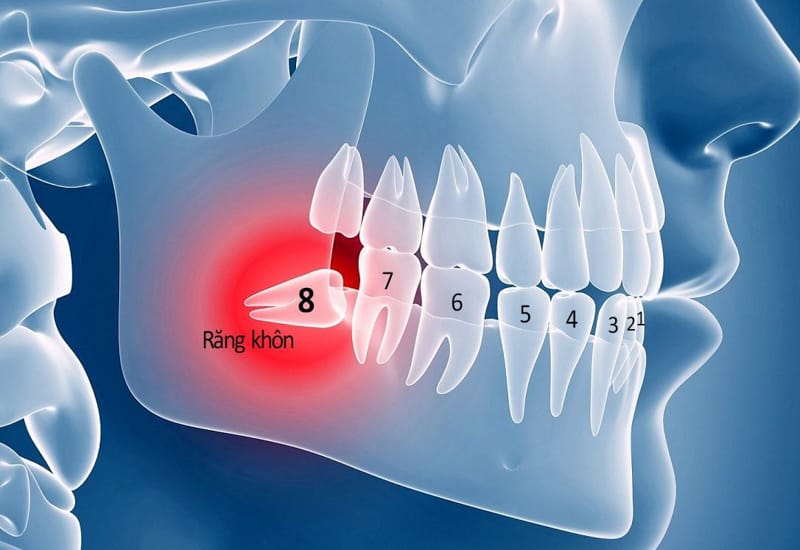

- Phân biệt theo vị trí: Răng khôn hàm dưới thường phức tạp hơn do gần các dây thần kinh quan trọng, do đó chi phí thường cao hơn so với răng khôn hàm trên.

- Phân biệt theo mức độ: Răng mọc thẳng có giá thấp nhất, răng mọc lệch có giá trung bình, và răng mọc ngầm, cần phẫu thuật, sẽ có mức giá cao nhất.

3.1. Tình trạng Mọc Răng Khôn

Độ phức tạp của ca nhổ là yếu tố số một ảnh hưởng đến chi phí.

- Răng mọc ngầm, chân răng cong: Đòi hỏi kỹ thuật và thời gian xử lý phức tạp hơn.

- Răng khôn gần dây thần kinh: Cần sử dụng máy chụp CT Cone Beam 3D để xác định chính xác vị trí, tránh tổn thương, do đó chi phí sẽ cao hơn.

- Tình trạng càng phức tạp, chi phí càng cao.

3.2. Vị trí Răng Khôn (Hàm Trên – Hàm Dưới)

Răng khôn hàm dưới thường có chi phí cao hơn răng khôn hàm trên. Lý do là hàm dưới có cấu trúc xương dày hơn, đồng thời vị trí nhổ thường gần dây thần kinh hàm dưới, yêu cầu độ chính xác và cẩn trọng cao hơn trong quá trình phẫu thuật.

4.2. Giá Nhổ Răng Khôn Mọc Lệch

Độ khó tăng lên do răng chỉ mọc một phần và bị nghiêng, thường đâm vào răng số 7. Bác sĩ cần phải rạch lợi và đôi khi phải chia nhỏ thân răng trước khi lấy ra, làm tăng thời gian phẫu thuật và chi phí cao hơn so với răng mọc thẳng.

4.3. Giá Nhổ Răng Khôn Mọc Ngầm, Phẫu thuật

Đây là nhóm chi phí cao nhất. Trường hợp này yêu cầu tiểu phẫu phức tạp, cần gây tê chuyên sâu, đôi khi phải khoan xương và cắt thân răng thành nhiều phần để lấy ra, đảm bảo không làm tổn thương cấu trúc xương hàm. Chi phí này bao gồm cả phẫu thuật, gây tê, và chăm sóc hậu phẫu kỹ lưỡng.